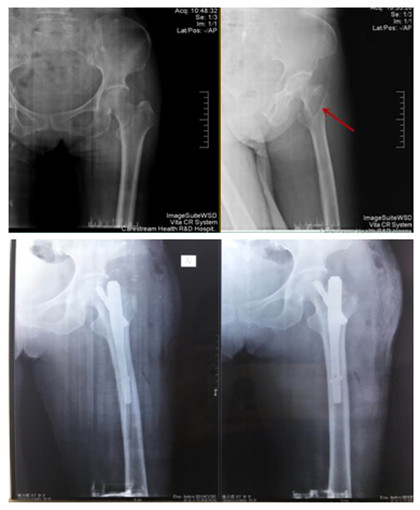

我院首例股骨粗隆間骨折PFNA技術(shù)